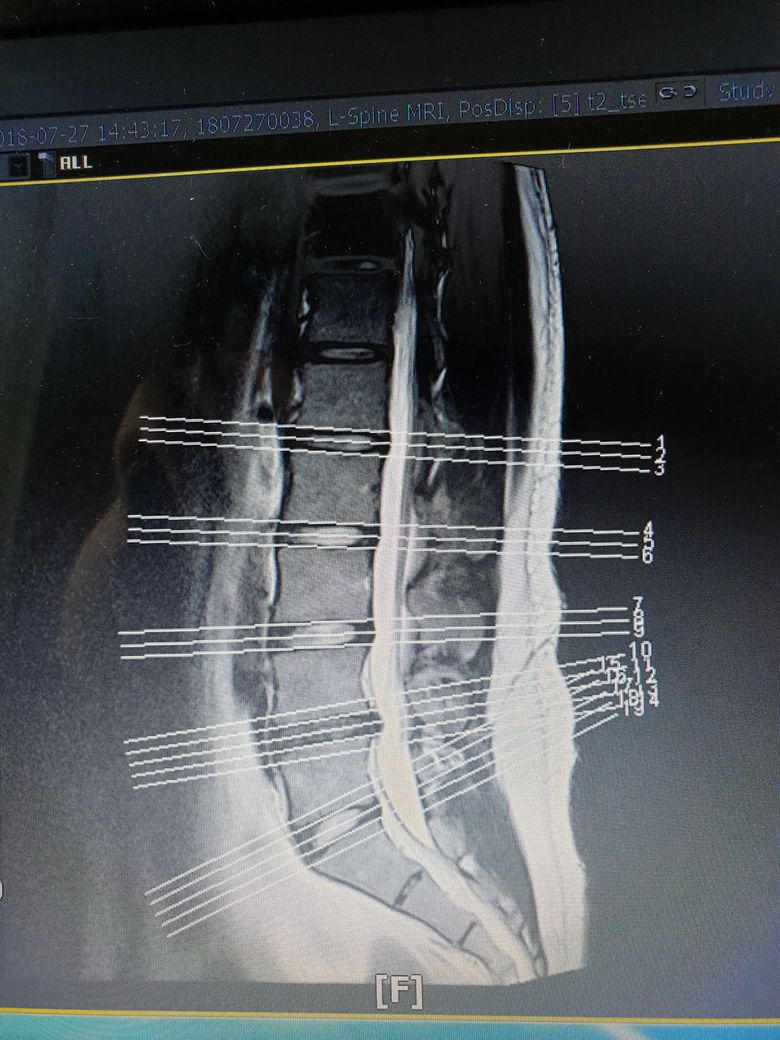

• 3번 째 사진

현재 mri에서는 3/4뿐만 아니라 4/5 디스크 역시 튀어나와있습니다. 물론 영상에서 보이는 소견도 중요하지만 증상도 중요합니다. 디스크는 가운데에 80%의 수분성분의 젤리처럼 생긴 수핵과 수핵을 보호하기 위해 섬유테들이 주위를 둥글게 감싸고 있습니다. 나이가 들어 수핵의 수분 함량 감소로 탄력성이 떨어지거나 외부적인 자극으로 디스크가 나오면서 신경을 눌러 통증을 일으킵니다. 젊은 연령층에서는 수핵의 탄력성이 유지되어있기 때문에 디스크가 나오더라도 다시 흡수되는 경우도 많이 있습니다. 일단 보존적 치료(물리치료, 재활운동, 보조기 착용, 주사 치료) 등으로 경과를 확인한 뒤 3개월 이상 보존적 치료에 효과가 없다면 수술적인 치료를 시행할수 있습니다.

4-5번은 이전에 어느정도였는지 알아야 얼마나 흡수됐는지 알 수 있습니다. 지금은 3-4번과 4-5번이 비슷한 정도로 튀어나와있습니다.

하지만 보여주신 sagittal view 만 봐서는 이렇게 튀어나간 디스크가 신경의 뿌리를 누르는지 아닌지 알아볼 수 없습니다. transverse view응 함께 봐야합니다.